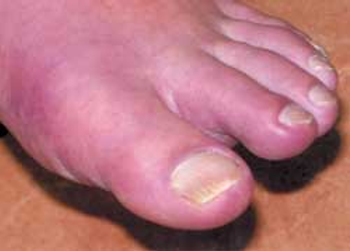

The faster the attack is recognized and treated with medications, the easier it is to control.

Once a disease of kings, gout affects an increasing number of “commoners”-and the physical and economic toll is high.

Elevated serum uric acid level is pathognomonic for gout. Untreated gout may lead to tophi, nephropathy, and uric acid nephrolithiasis.